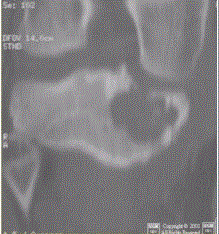

问题 患者男,15岁。右膝X线平片和CT检查见下图。 根据此病灶内部多发钙化,对其定性诊断的提示是

选项 A.良性 B.骨源性 C.软骨源性 D.纤维源性 E.恶性

答案 C